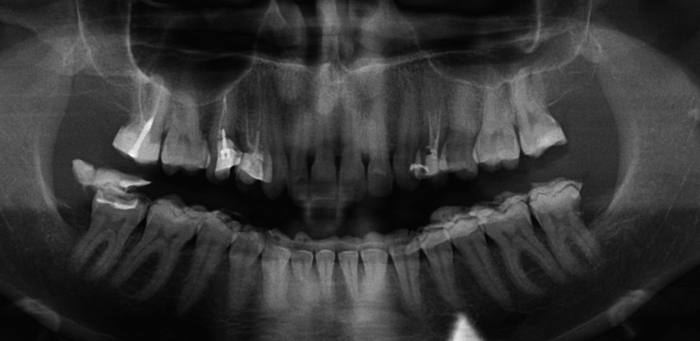

Единственный снимок, который нашла, не помню, болел на нём уже зуб или ещё нет, ну прикус был ещё неправильный.